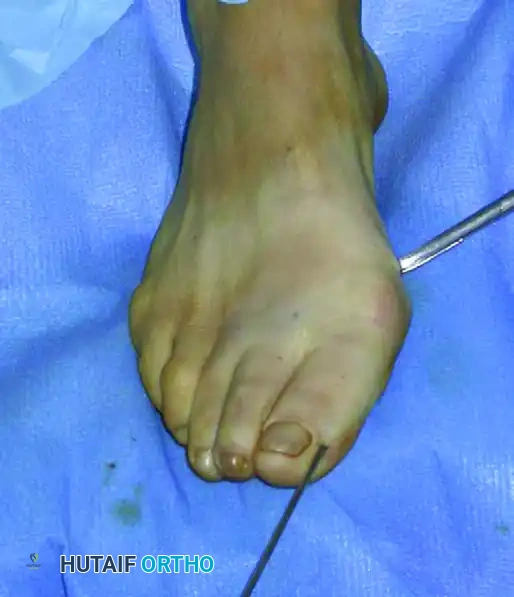

إزاحة العظم وتصحيح الانحراف

بمجرد الوصول إلى التصحيح المطلوب، يتم دفع السلك المعدني بعمق داخل القناة العظمية لتثبيت العظم في وضعه الجديد والمستقيم.

تثبيت العظم في الوضع الصحيح الجديد